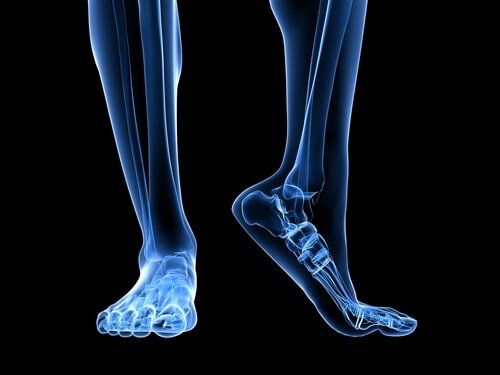

التهاب الرباط الأخمصي يصيب اللفافة الأخمصية للقدم؛ رباط يصل بين عظم الكعب والسلاميات الدنيا لأصابع القدم، ويتمدد وينقبض مع كل خطوة، كعصابة مطاطية.

الرباط الأخمصي نسيج عريض وسميك جدًا بسبب الوزن والضغط الهائل الموضوع عليه طوال الوقت مع الحركة.

تشريح القدم

تلعب عدة هياكل تشريحية مختلفة دورًا في الضغط المفرط على الرباط الأخمصي.

وتر أخيل هو رباط يصل بين عضلة الساق، والمعروفة بالربلة، والعضلية النعلية، وعظم الكعب.

انقباض وتر أخيل يضع ضغطًا زائدًا على عظم الكعب، مما يؤدي بدوره إلى زيادة الضغط على اللفافة الأخمصية.

فيما يتعلق بالهياكل التشريحية، يجب أخذ عامل آخر في الاعتبار، ألا وهو ضربة القدم، أو كيفية لمس القدم للأرض أثناء الحركة.

القدم المسطحة التي تميل إلى الكَبّ تسبب تمدد اللفافة الأخمصية أكثر، وهو ما يزيد خطر الإصابة بالتمزقات والألم.